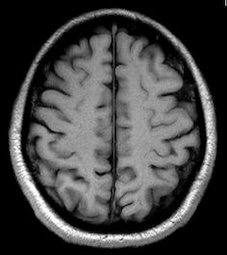

The Brain Tumor MRI Images dataset is a publicly available dataset on Kaggle555https://www.kaggle.com/datasets/sartajbhuvaji/brain-tumor-classification-mri/data. It contains MRI images of human brains divided into four categories: No Tumor, Pituitary Tumor, Benign Tumor, and Malignant Tumor. For our study, we selected three categories: No Tumor (NT), Benign Tumor (BT), and Malignant Tumor (MT). From each category, we chose three MRI images representing different parts of the brain that best illustrate the characteristics of each class. The categories included in this study are described as follows:

The No Tumor (NT) category contains MRI images of healthy brains with no abnormal growths or masses. In these images, the brain tissue appears normal, and there are no signs of tumors or unusual structures. These images serve as a baseline, allowing for effective comparison and detection of abnormalities in other MRI scans.

Refer to caption

(a) NT1

(b) NT2

(c) NT3

Figure 5. Axial and Coronal MRI Images of Brains Representing Different Tumor Categories

Differentiating these categories is essential for early detection, accurate diagnosis, and effective treatment planning. By distinguishing between healthy brains, benign tumors, and malignant tumors, medical professionals can identify abnormalities more reliably, reduce misdiagnoses, and streamline medical care. In this study, we apply our divergence measure to differentiate between the selected MRI images, as illustrated in Figure 5. In Figure 5, the first row shows MRI images from NT patients, the second row shows images from BT patients, and the third row shows images from MT patients.

Using the divergence measure, we calculated estimates for each pair of MRI images and compared the three categories. For calculation, each grayscale image is represented by its pixel intensity values (scaled to [0,1]). These values are flattened into a one dimensional vector and used as the sample data for subsequent analysis. For any two images, denoted data1 and data2, we then computed an empirical based divergence estimate. The resulting values are presented in Tables 4, 5, and 6. A higher value of the divergence estimate indicates a greater likelihood of a tumor. These results demonstrate that the divergence measure can serve as an effective tool for detecting tumors in medical image data.